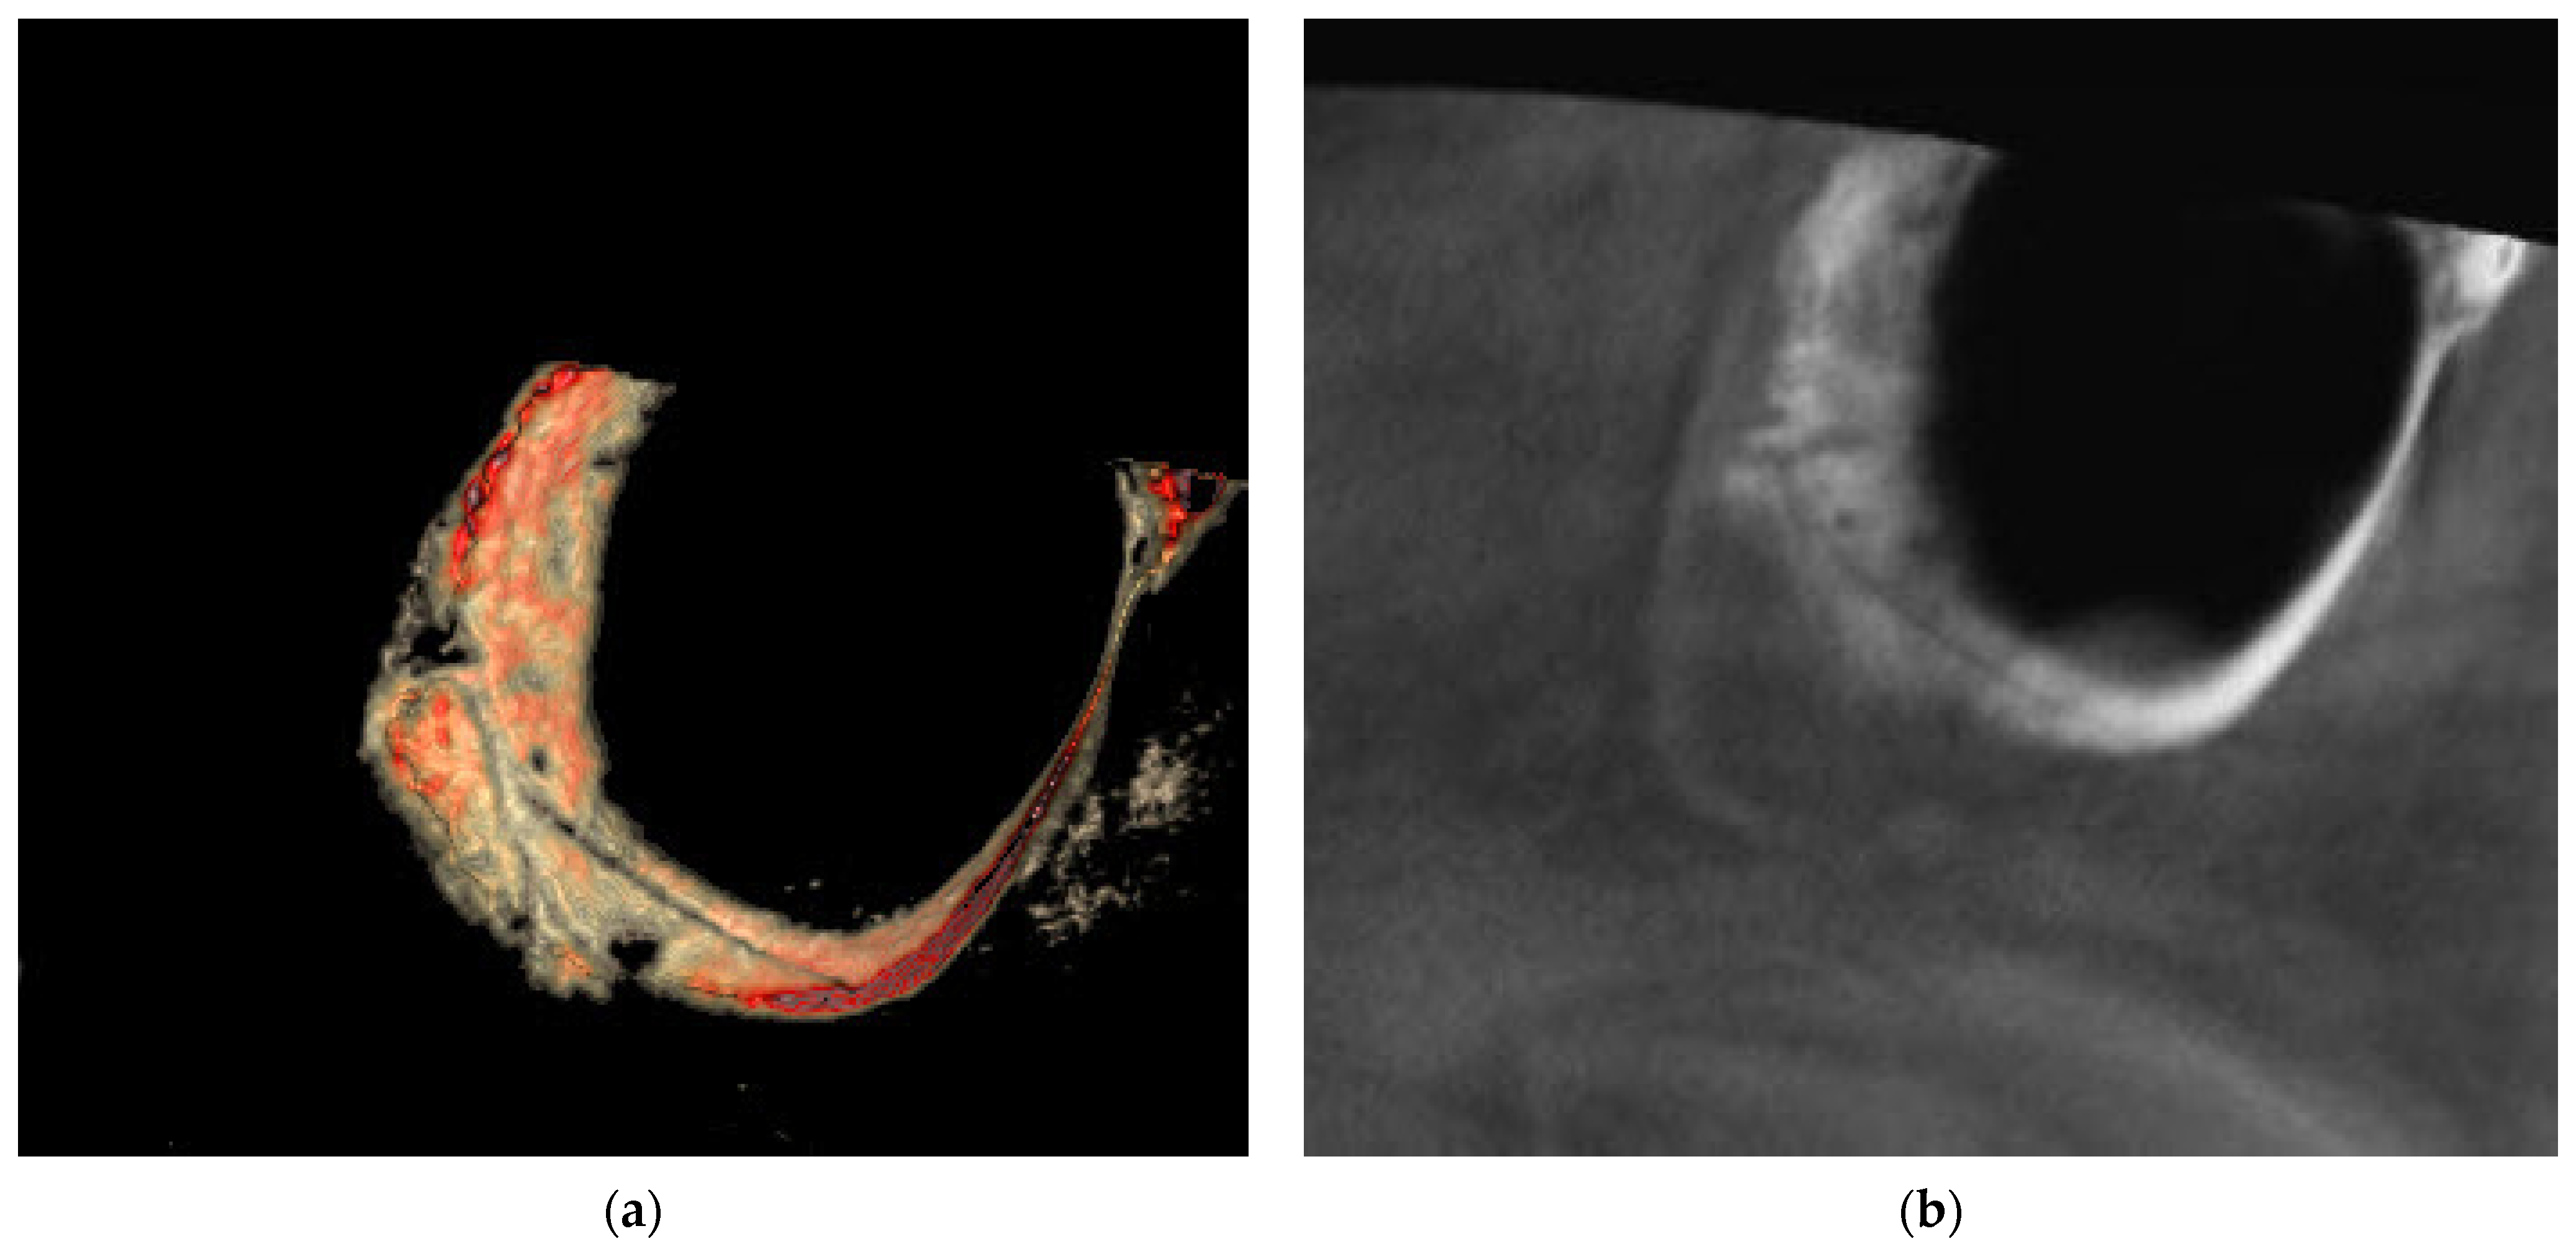

2.2. Radiographic Analysis